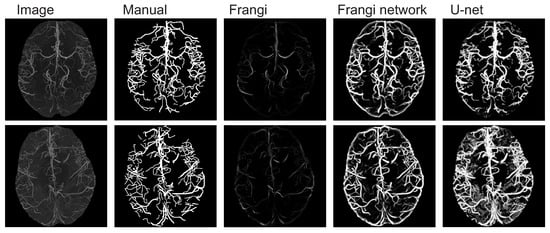

2.4.3. Brain MRA (Brain)

3. Results